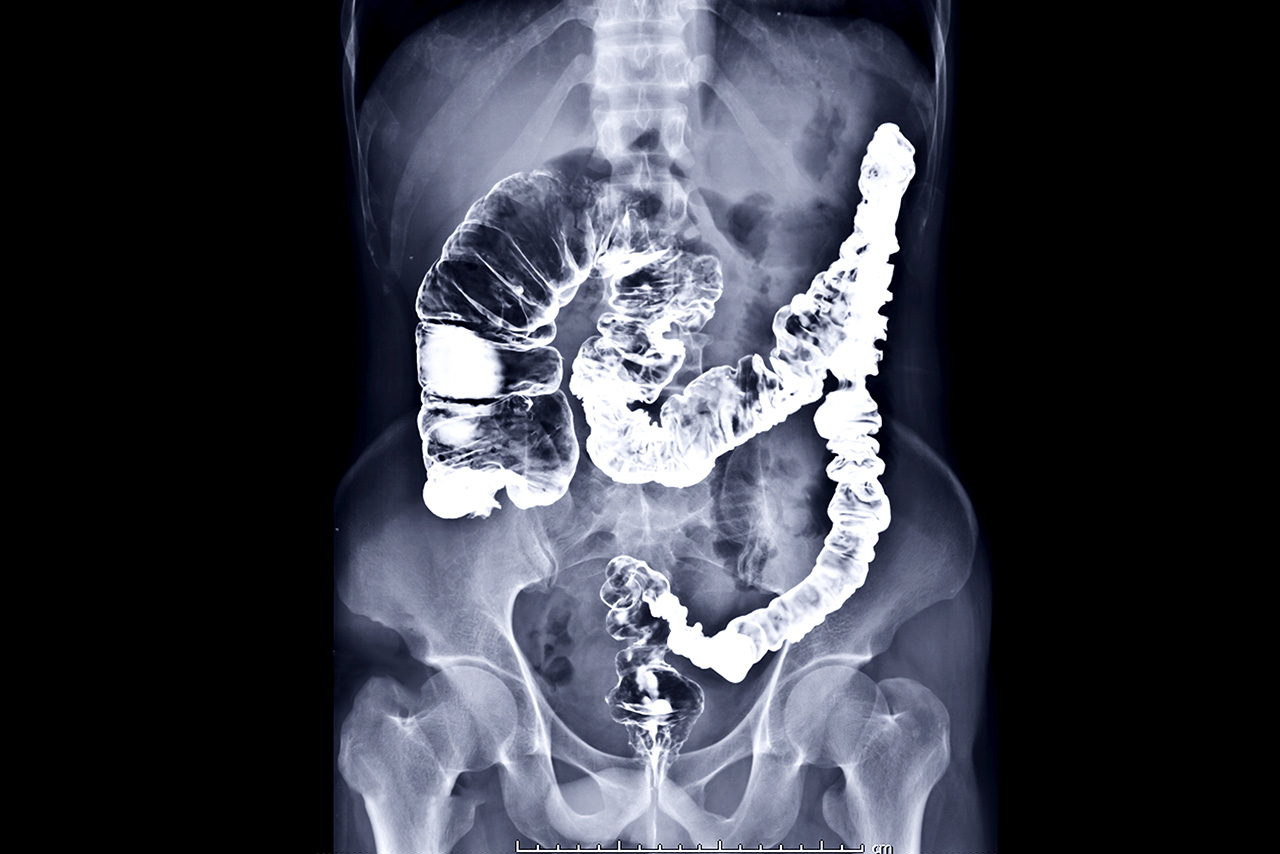

The best known field using man-made radioactivity sources is medicine. It employs ionizing radiation both for diagnostics and for treatment. X-rays are used for diagnostics either in its classical form of images or in the more sophisticated form of computer tomography. Injecting a radioactive isotope into the bloodstream allows a perfect imaging of blood vessels. Radioisotopes are commonly used as markers. They are combined with a substance that is trapped in certain types of tissue (thyroid gland, tumor, etc.) and then using a scintigraph, the entire area is clearly visualized because of its accumulated radioisotopes. Large doses of radiation are used to treat and eliminate tumors.